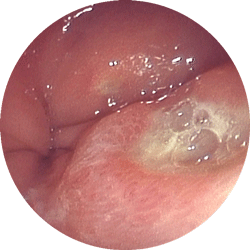

胃潰瘍

食欲不振で来院

内服薬1ヶ月で治癒